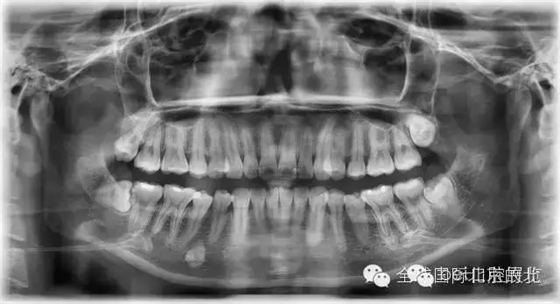

常規(guī)X-RAY全景片檢查

一個病人進來我們不單單要關注患牙,而且要關注他們全口的牙齒情況,卡瓦的跨學科病例大賽讓我更加重視了患者的全局觀,雖然患者暫時不一定會處理,但是作為我們醫(yī)生有必要告訴他們,選擇權交給患者自己,也希望和所有醫(yī)生共勉。